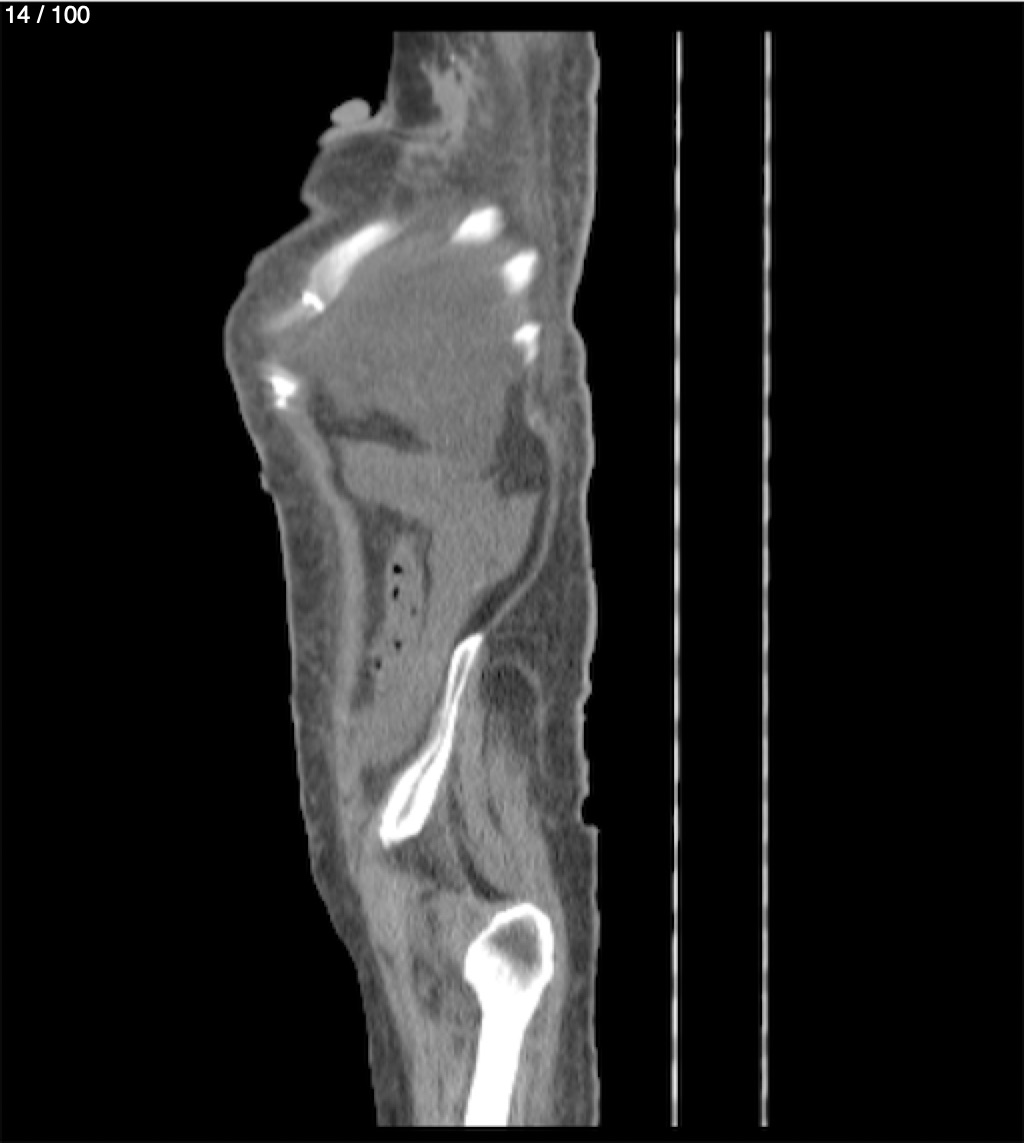

Hilda Geronimo Mendez 60A - T.C Abdomen Simple